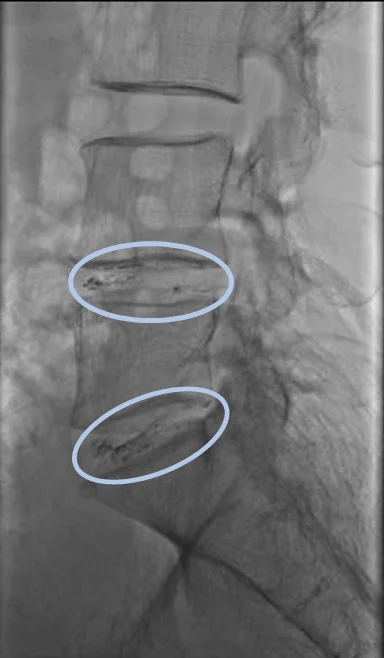

По данным МРТ выявлены левосторонние межпозвоночные грыжи дисков L4/L5 и L5/S1.

Предполагается, что грыжи дисков L4/L5 и L5/S1 являются основной причиной болей в пояснице, а также болей и онемения в левой ноге.

Проведена селлгель-терапия на дисках L4/L5 и L5/S1.